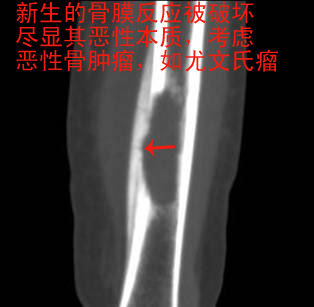

男孩,5岁,左小腿疼痛,肿胀,活动受限20天。

左胫骨中下段见一长卵圆形骨质破坏区,走形方向与胫骨长轴一致,边缘轻度硬化,内后侧骨皮质破坏,伴明显骨膜增生,破坏区内呈软组织密度。未见明显软组织肿块。

鉴别:本病主要与胫骨恶性肿瘤,尤其尤文氏瘤鉴别。后者骨质破坏范围更广、破坏区边缘往往不规则,骨膜增生更明显、骨膜增生可见较明显的骨质破坏,放射状骨针常见,多见软组织肿块。一般可以鉴别,当然确诊有赖于病理学检查。另外,与骨髓炎等鉴别不难。

支持恶性骨肿瘤,以尤文氏瘤可能性大.

病史资料不完善,根据年龄、部位、及影像学表现,主要表现胫骨骨干囊性骨质破坏,骨皮质受累,局部骨膜反应,未见骨膜破坏及瘤骨,未见放射状骨针。 首先要考虑胫骨转移瘤,建议进一步检查,除外视网膜母细胞瘤,神经母细胞瘤,肾母细胞瘤,肾上腺等恶性肿瘤骨转移。排除转移瘤后考虑嗜酸性肉芽肿可能性大,患者年龄5岁,尤文氏瘤不太考虑,骨肉瘤也不太符合,骨髓炎待排,影像表现不太支持。建议进一步检查,除外原发恶性肿瘤胫骨转移后,考虑嗜酸性肉芽肿。必要时穿刺活检。

小孩的骨膜反应及骨质增生均比较活跃,应考虑这个因素与恶性肿瘤来鉴别,葱皮样明显增厚的骨膜反应不见得一定是恶性表现,特别是弥漫增厚的更提示炎症可能性较大;恶性的骨膜增厚往往是以局部增厚明显并有软组织肿块或者骨膜三角形成的表现较为肯定。本例考虑还是肉芽肿可能性较大。